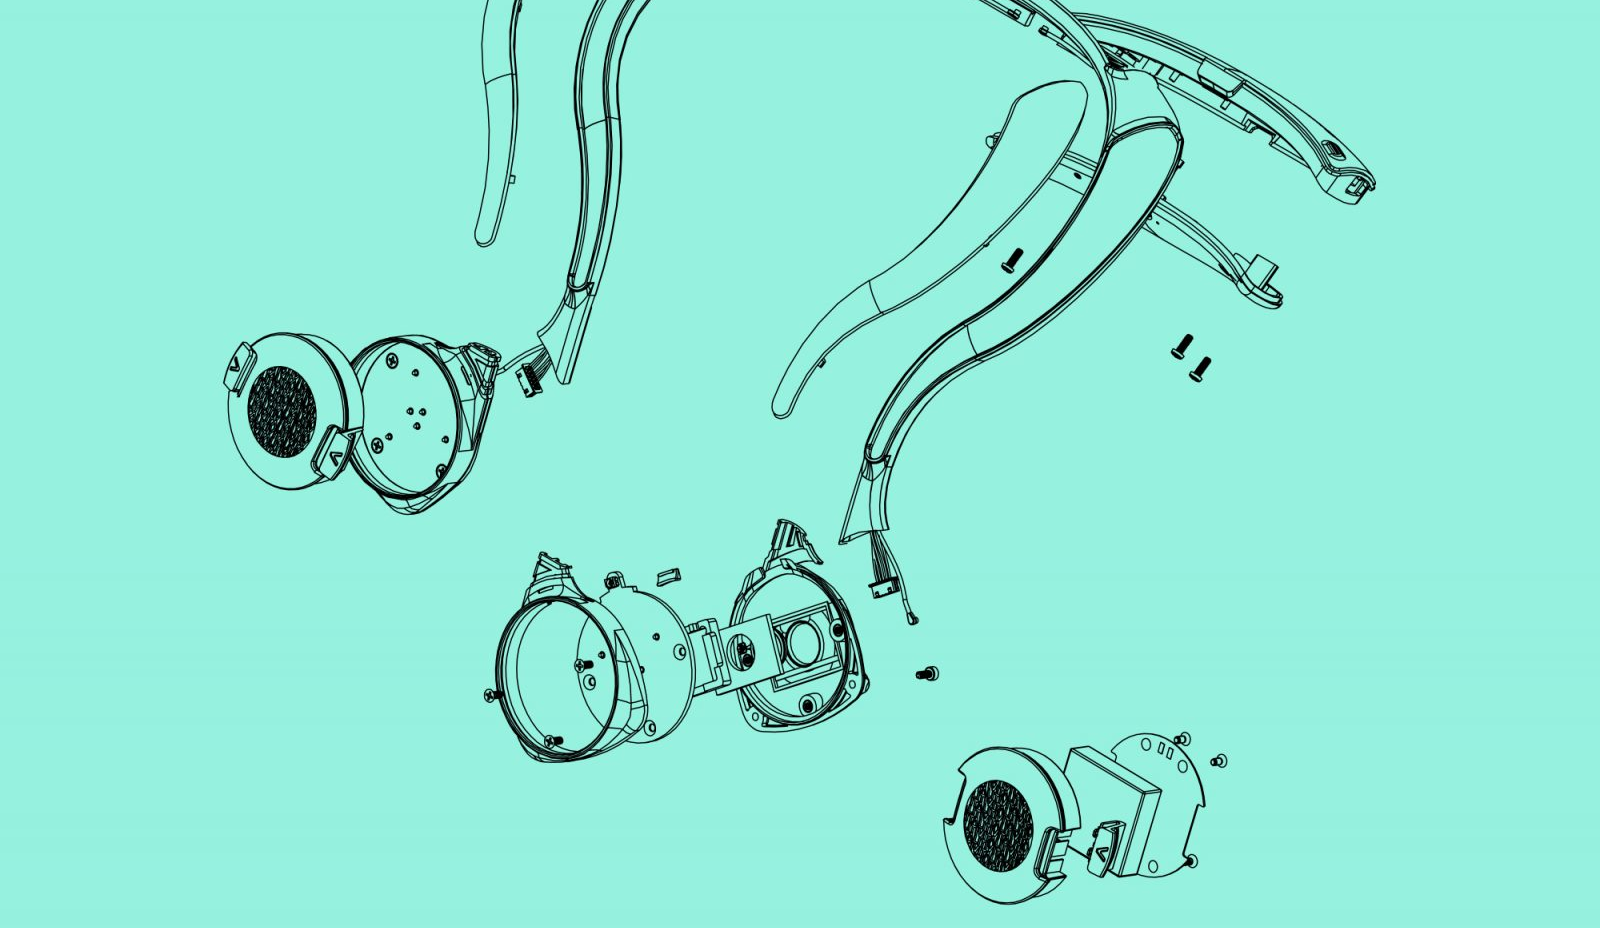

- How to bridge several data collection points on a patient’s collarbone and ear in a single wearable.

- The wearable had to collect all five human vital signs continuously for three days. We realized our wearable had to be easy to charge without the user having to take it off.

- In-house firmware electronics and biometric software algorithm integrated very tightly with industrial design and mechanical engineering.